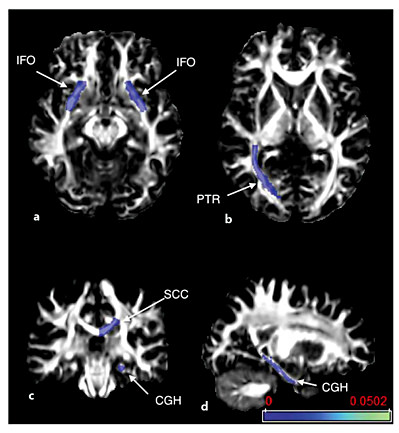

Eleven white matter association area tracts on each side were chosen for analysis (fig. 1), including the uncinate fasciculus, superior longitudinal fasciculus (SLF), superior fronto-occipital fasciculus (SFO), inferior fronto-occipital fasciculus (IFO), posterior thalamic radiation (PTR), and the fornix. The corpus callosum was segmented into three portions: the genu, body, and splenium. The cingulum was segmented into the portion underlying the cingulate cortex and a hippocampal portion. These association tracts were chosen because of literature suggesting their association with the cognitive tests used, or because of their involvement in ALS or FTLD. The corticospinal tract was not included in the analysis, as the changes associated with ALS and PLS diagnoses and motor function have been previously reported for these patients [23].

FA maps with color overlays showing the white matter tracts included in the analysis. Tracts were segmented by atlas analysis. The evaluated tracts were the uncinate fasciculus (UNC), SLF, SFO, IFO, PTR, and the fornix (Fx). The corpus callosum was segmented into three portions: the genu, body, and splenium (GCC, BCC, and SCC). The cingulum was segmented into the portion underlying the cingulate cortex (CGC) and a parahippocampal portion (CGH).

FA maps with color overlays showing the white matter tracts included in the analysis. Tracts were segmented by atlas analysis. The evaluated tracts were the uncinate fasciculus (UNC), SLF, SFO, IFO, PTR, and the fornix (Fx). The corpus callosum was segmented into three portions: the genu, body, and splenium (GCC, BCC, and SCC). The cingulum was segmented into the portion underlying the cingulate cortex (CGC) and a parahippocampal portion (CGH).

Axial (a, b), coronal (c), and sagittal (d) views of FA maps with color overlays of white matter structures with significant associations between DTI metrics and particular neuropsychological tests as listed in table 4. The DRS-2 memory subscore was associated with AD of the IFO bilaterally (a), and the right PTR was associated with the memory score and letter fluency (b). Other fluency subscores were associated with diffusion properties of the splenium of the corpus callosum (SCC) (c) and the parahippocampal portion of the left cingulum (CGH) (d). Scale denotes uncorrected p value, and thresholds below 0.01 are shown.

Axial (a, b), coronal (c), and sagittal (d) views of FA maps with color overlays of white matter structures with significant associations between DTI metrics and particular neuropsychological tests as listed in table 4. The DRS-2 memory subscore was associated with AD of the IFO bilaterally (a), and the right PTR was associated with the memory score and letter fluency (b). Other fluency subscores were associated with diffusion properties of the splenium of the corpus callosum (SCC) (c) and the parahippocampal portion of the left cingulum (CGH) (d). Scale denotes uncorrected p value, and thresholds below 0.01 are shown.